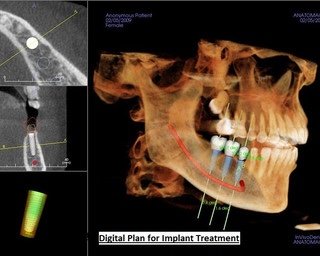

Burute Dental Clinic is the best dental clinic in Pimpri Chinchwad (PCMC) Pune, led by Dr. Mrunal Burute and Dr. Madhura Burute, expert implant dentists. We specialize in dental implants, full mouth dental implants, all-on-4, all-on-6, all-on-X implants, single tooth implants, immediate dental implants, and complex dental implant cases with high success rates. Known as a top dental implant clinic near me, we treat failed implants, severe bone loss, and advanced full mouth rehabilitation cases with precision. Our dental care services include root canal treatment, painless RCT, teeth whitening, aligners, braces, pediatric dental care, cosmetic dentistry, and complete oral care. If you are searching for dental implants near me visit us